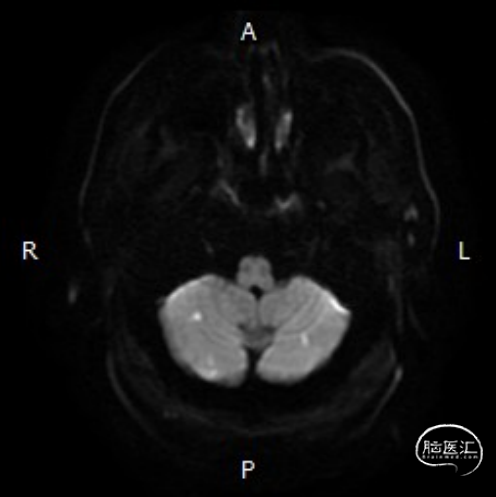

➢头颅MRI:

双侧小脑半球以及桥脑急性缺血性梗死。